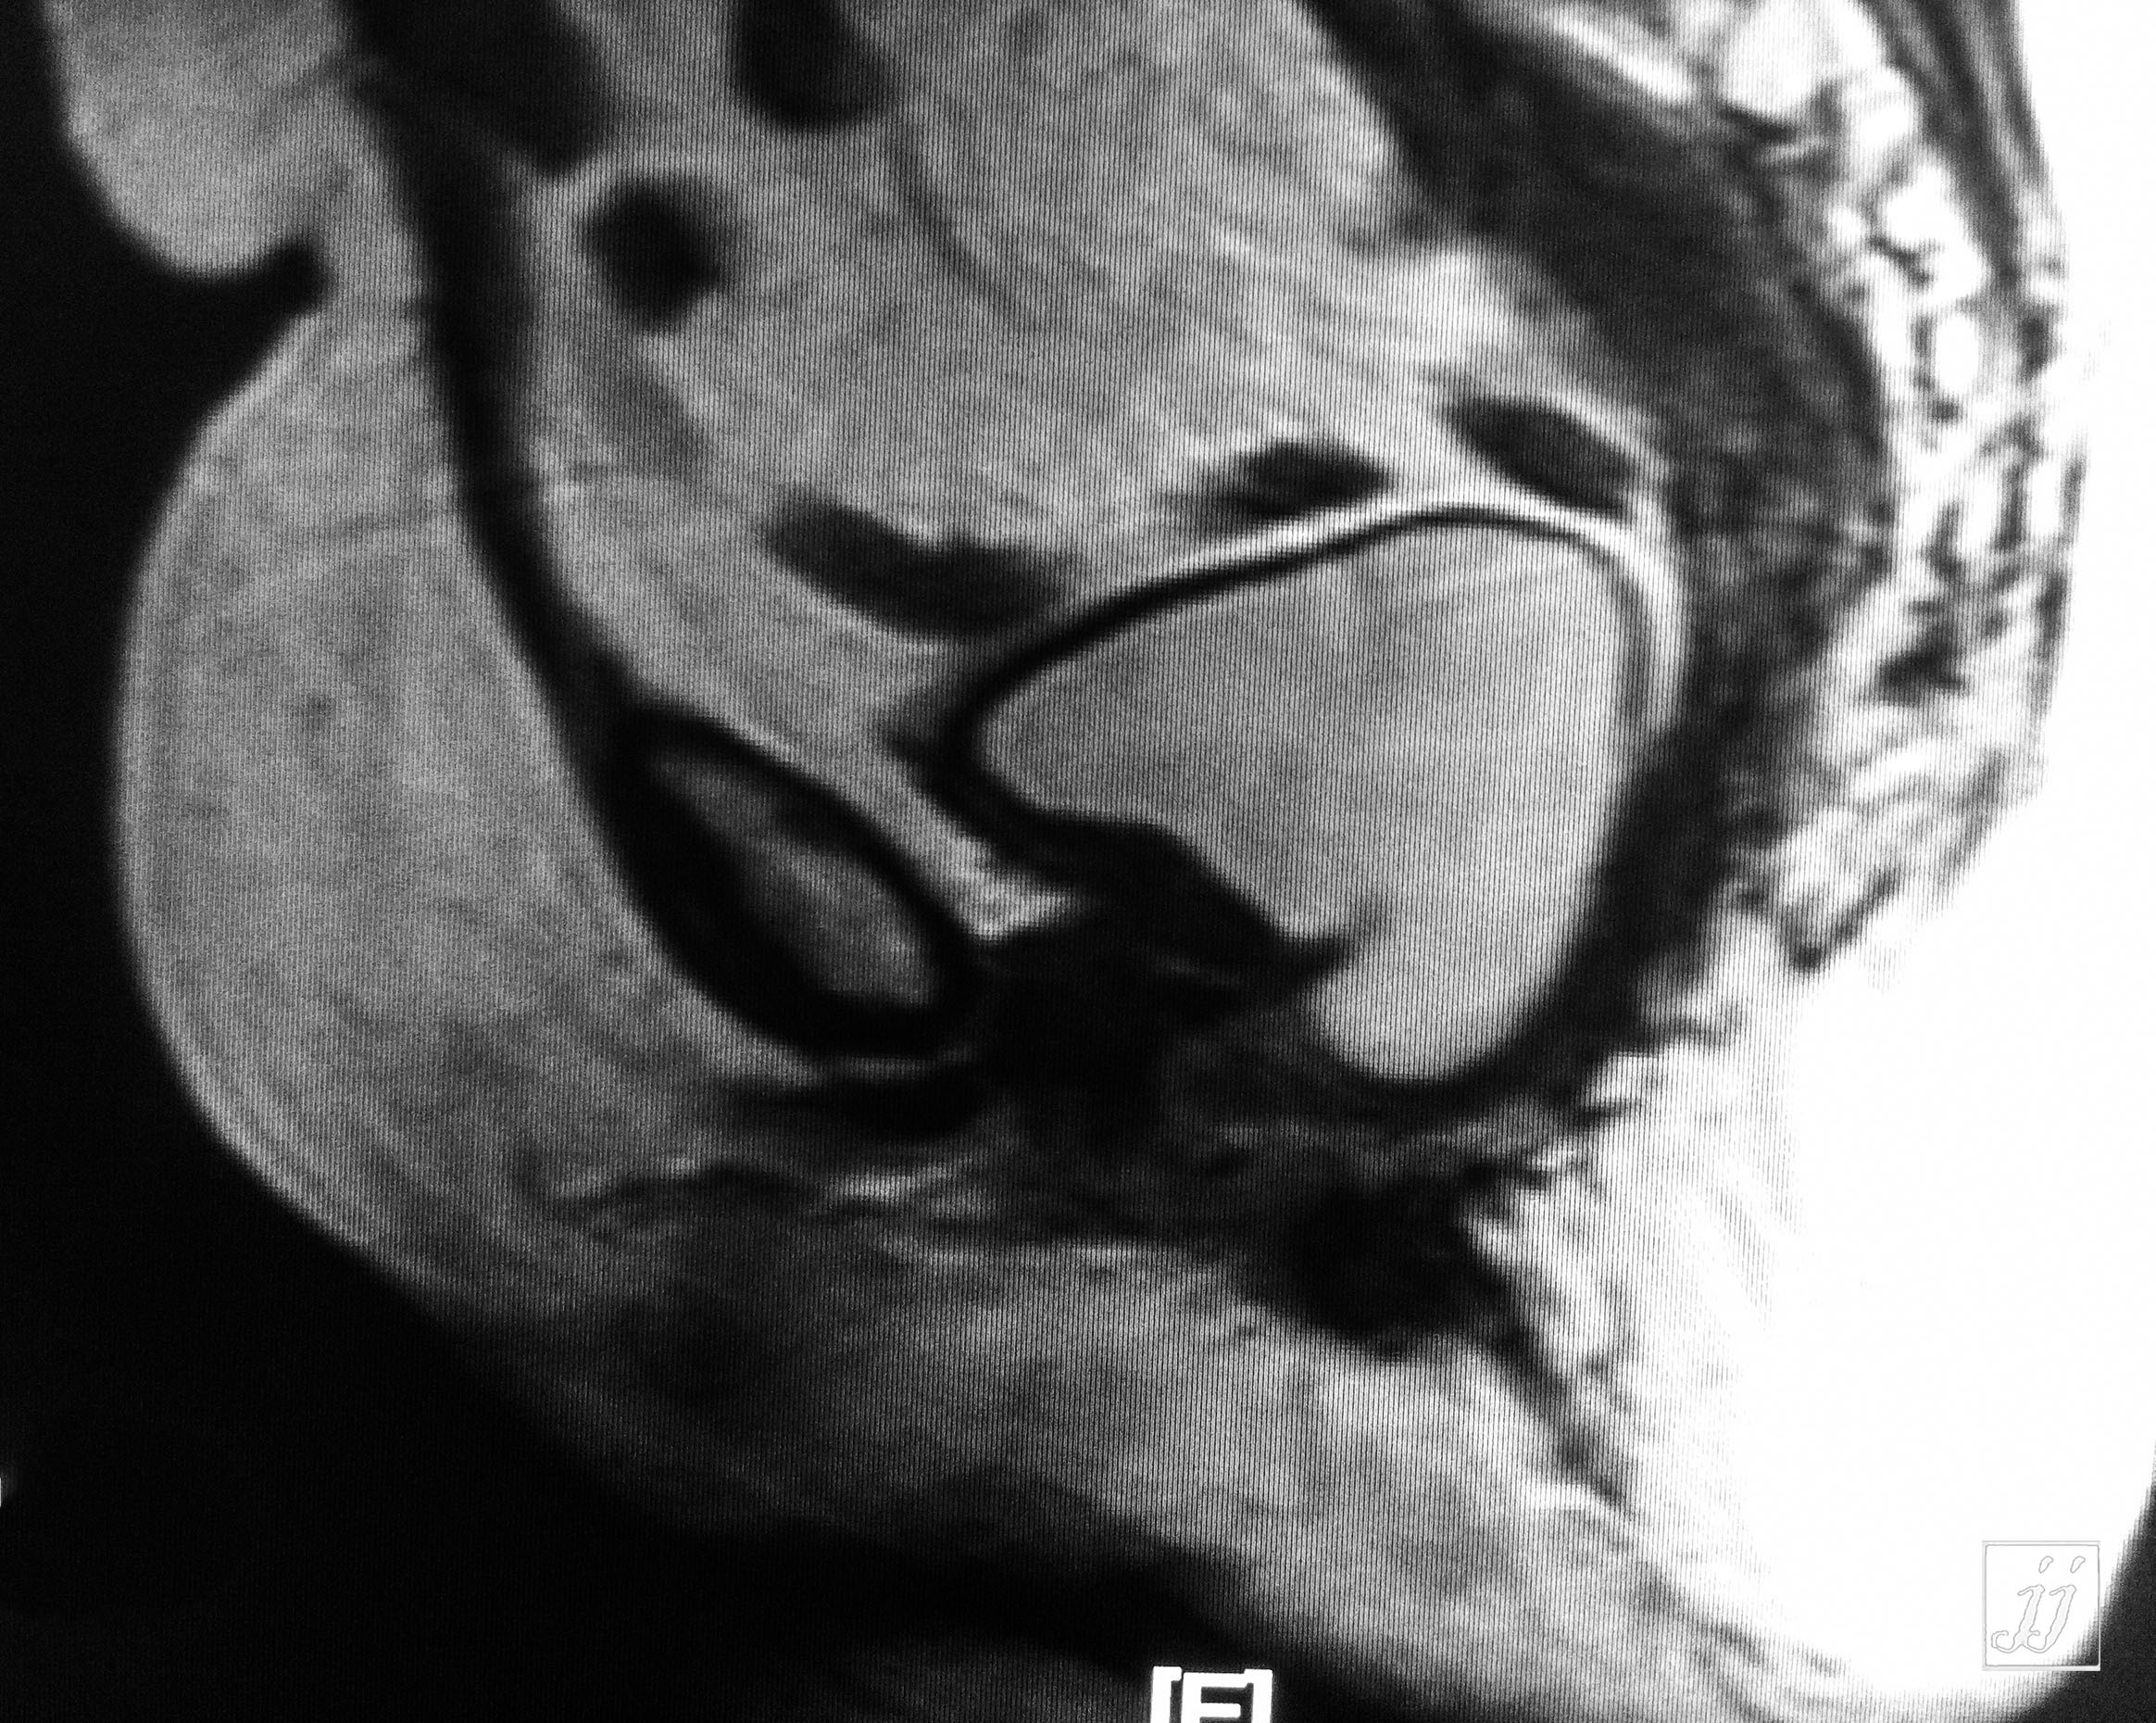

Abdomen- urinary bladder tumor (2)